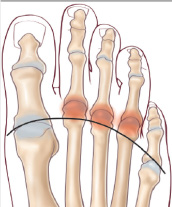

En raison de sa déformation, le premier orteil perd progressivement ses fonctions d’absorption des charges lors de l’appui et de propulsion lors du passage du pas. Cela se répercute sur les orteils latéraux qui sont, par conséquent, plus sollicités. Des douleurs d’hyper-appui sous les têtes des métatarsiennes (métatarsalgies) peuvent apparaître, avec formation de durillons plantaires, ainsi que des déformations en griffe des orteils. Ces derniers peuvent donc aussi créer des conflits entre eux, et dans la chaussure avec formation de durillons, souvent douloureux.

• Les griffes

• Les métatarsalgies